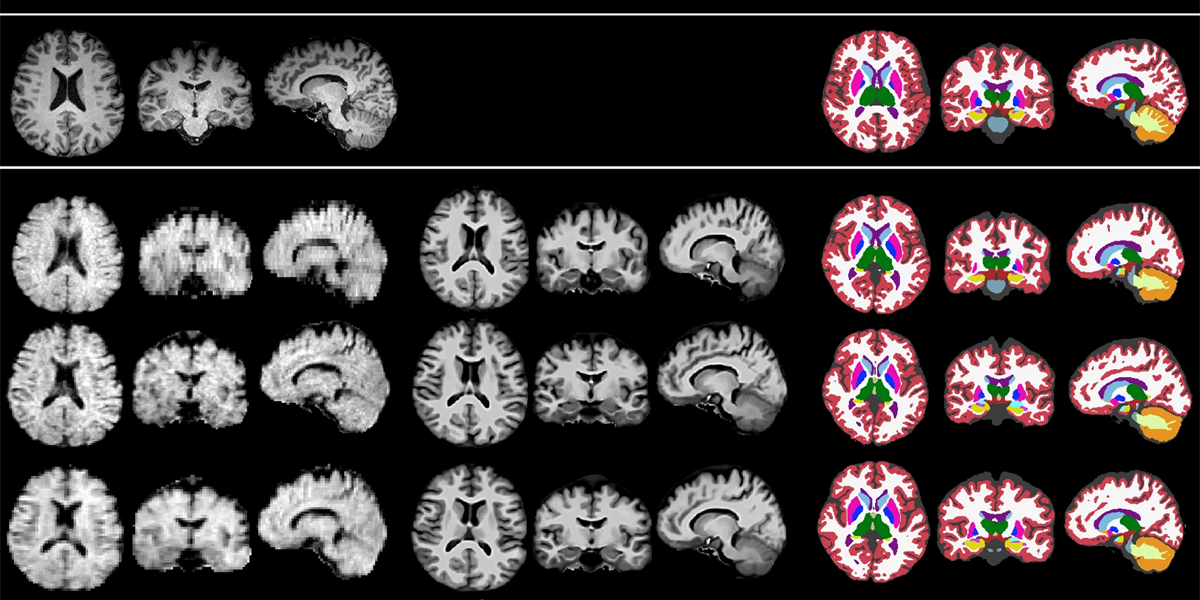

In a previous studyThe team created an AI model that could improve low-quality scans taken with a portable, low-field MRI machine down to the crucial 1-millimeter resolution. The researchers found that the high-resolution images generated matched well with actual high-resolution images taken from a small group of patients.

In addition to increasing the quality of images acquired using low-field MRI, the researchers also developed fully automated programs to identify different brain regions and then calculate the volume of the parts of interest. In the new work, the authors increased the difficulty by implementing low-field MRI scans and their machine learning tools on a larger number of people, including many patients with Alzheimer’s disease or mild cognitive impairment (MCI).

In particular, they used their automated approach to calculate the size of the hippocampus and lateral ventricle, regions of the brain that are often altered in Alzheimer’s disease. They also used the system to identify and measure lesions in the brain, called white matter hyperintensities, also linked to Alzheimer’s. Monitoring changes in these regions is useful both in diagnosing and monitoring the progression of degenerative conditions.

Across experiments with nearly 100 subjects, the results from their AI-enhanced low-field MRI system were on par with measurements taken with conventional high-field machines. The authors showed that both methods could distinguish the brains of subjects with Alzheimer’s disease or mild cognitive impairment from those who were healthy with a similar level of accuracy.